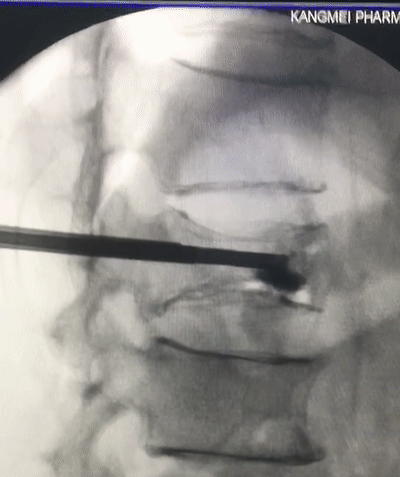

在我院先進的術中三維CT引導下,杜教授确定L1雙側椎弓根進針點,娴熟地将穿刺針穿入L1椎體,經穿刺針建立通道将約11ml骨水泥注入坍塌的椎體中。術中監視,注入的骨水泥逐漸支撐起原本壓縮空洞的椎體。骨水泥凝固後,病變的椎體迅速恢複了承重能力。手術持續約40分鍾,開展非常成功,術後老人的疼痛馬上消失,翻身也無疼痛,第二天就能使用助步器下地行走。

△術中注入骨水泥約11ml